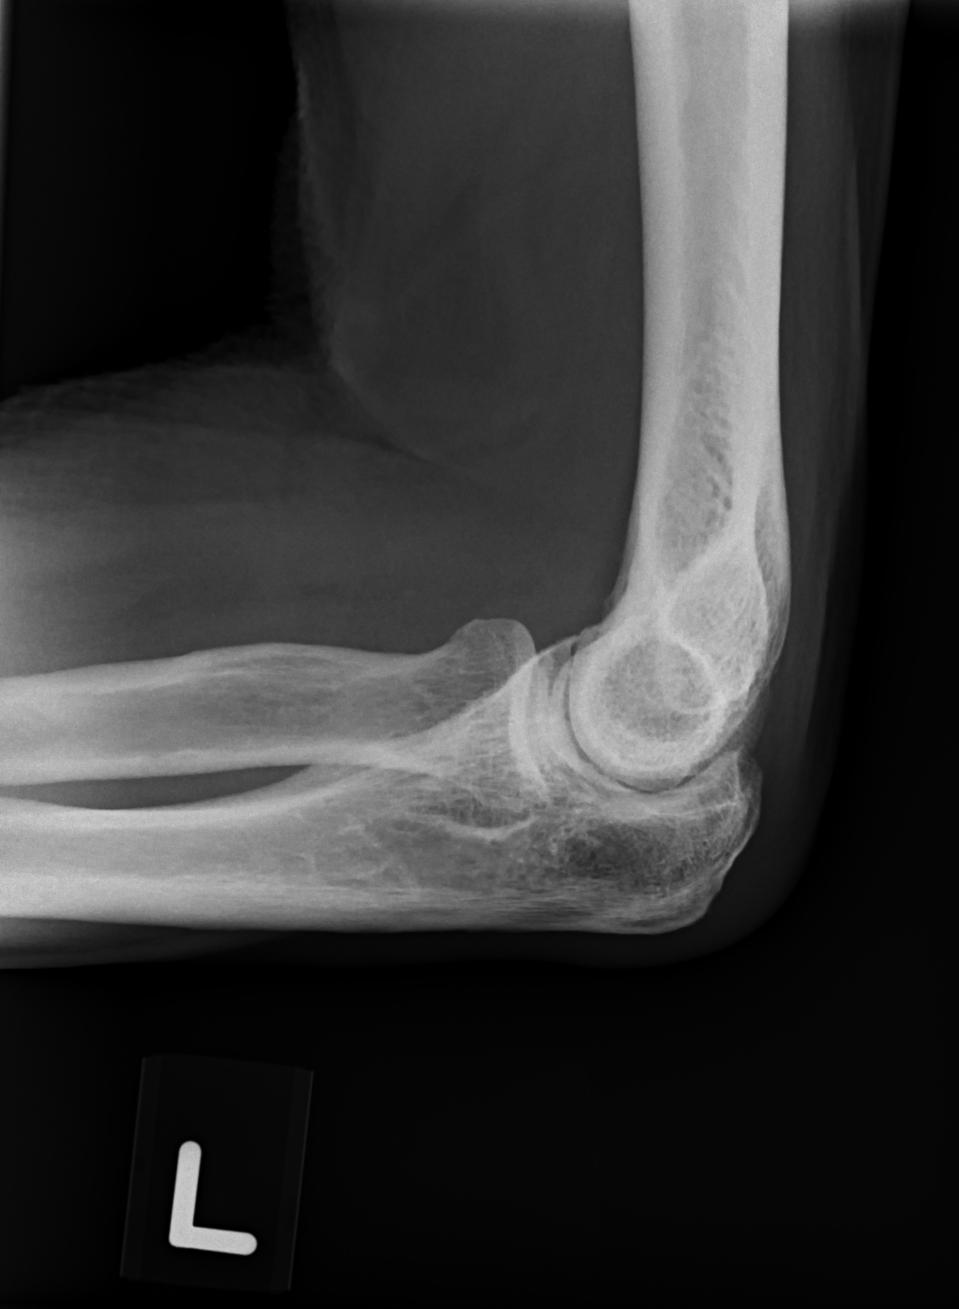

| Patient: TAY LIANG KWANG (M) | Birth date: 10/31/1949 | ID: S0185622G |

| Study | ID | Date | Accession # | Thumbnails | Report | XR ELBOW, AP & LAT, LEFT | 2766356 | 08/21/2019 | 2766356 | ... | MR WHOLE SPINE (FULL STUDY) | 32376 | 08/23/2019 | 2766095 | ... | XR CERVICAL SPINE, AP & LATERAL | 2765876 | 08/20/2019 | 2765876 |